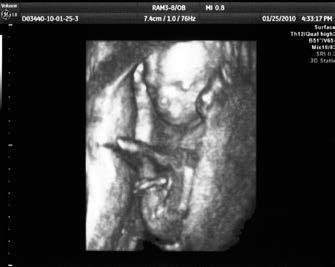

Vývoj plodu, 16. týden těhotenství (3D ultrazvuk)

První trimestr končí ve 13. týdnu těhotenství. V této době měří plod zhruba 10 centimetrů a váží 20 gramů. Zevní tvar plodu je již plně vyvinut, ledviny plodu začínají tvořit a vylučovat moč. Aktivní pohyby plodu, které jsou již na ultrazvuku patrné, však matka ještě nevnímá.

V 16. týdnu těhotenství je plod pokryt drobným chmýřím, rostou mu řasy a obočí. Kůže je tenká, průhledná. Začínají se tvořit pevné kosti, funkční jsou i klouby. Pohyby plodu jsou velmi živé, ale těhotná žena je ještě obvykle necítí. Začínají být patrné i pohlavní orgány. Na ultrazvuku je však lze rozlišit až o dva až tři týdny později.